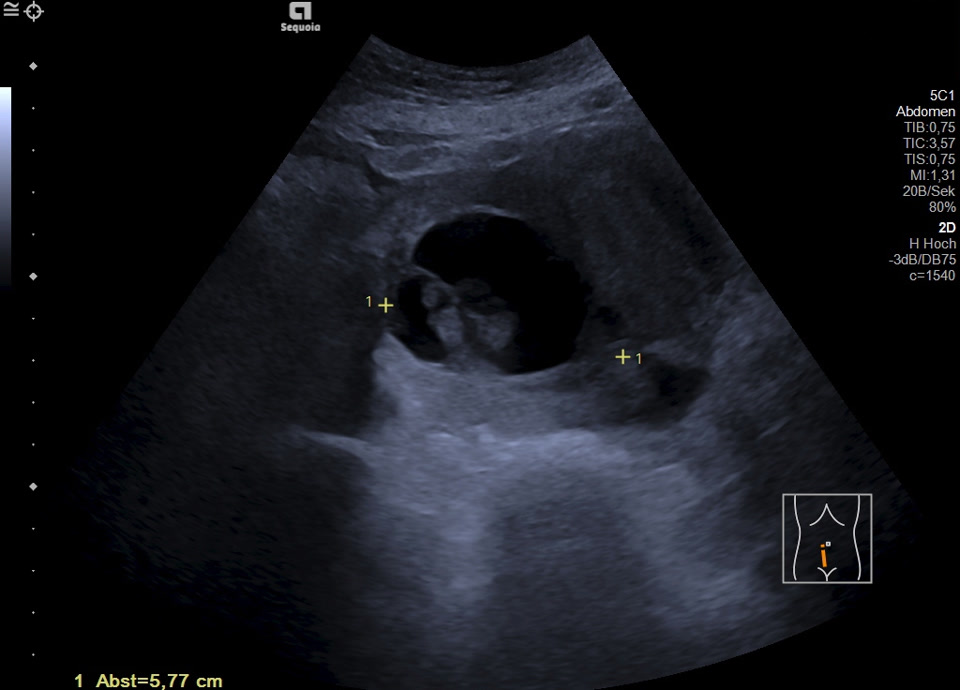

Es zeigt sich subkapsulär in Segment VI der Leber eine zystische Raumforderung mit durchgehendem Kapselreflex und hyperechogenem solidem Anteil. Der Befund ist nicht vereinbar mit einer blanden Zyste, sondern suspekt auf eine zystisch-solide Metastase. In der ergänzenden CEUS nehmen die soliden Anteile in der arteriellen Phase Kontrastmittel auf und zeigen in den portalvenösen sowie späten Phasen eine persistierende KM-Anreicherung ohne Washout. Zusätzlich finden sich eine noduläre Peritonealverdickung im Oberbauch sowie ein zystischer Ovarialtumor mit soliden Anteilen im rechten Unterbauch. In Zusammenschau der Befunde besteht der dringende Verdacht auf ein hepatisch und peritoneal metastasierendes Ovarialkarzinom.